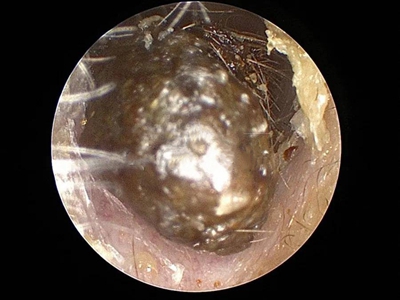

外耳道耵聍栓塞耳内完全堵塞图

外耳道耵聍栓塞患者外耳道分泌物干燥后形成碎屑或薄片,大量堆积后在鼓膜前方形成多层硬结,随着时间延长,颜色逐渐加深,呈褐色或红褐色。